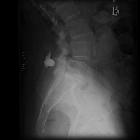

Plain radiograph and CT

- often shows close approximation and contact of adjacent spinous processes (kissing spines)

- resultant enlargement, flattening, and reactive sclerosis of apposing interspinous surfaces